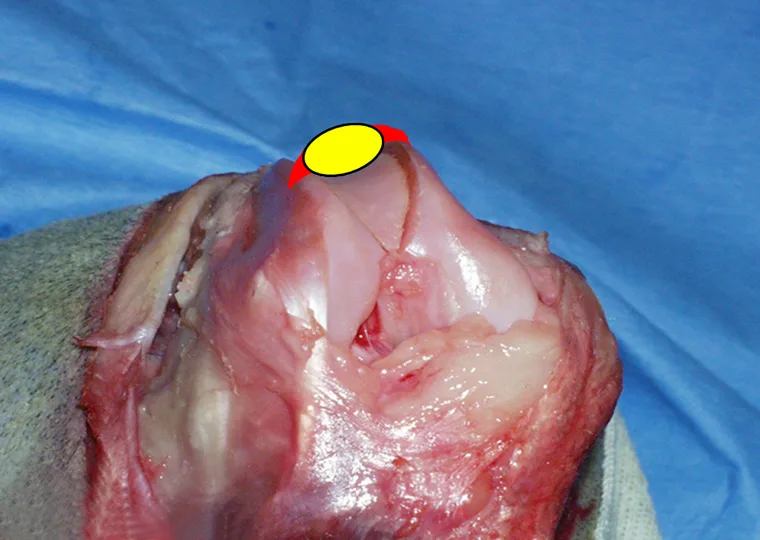

I typically perform a lateral arthrotomy because imbrication of the soft tissues on the lateral side is necessary. Once the arthrotomy is performed, the trochlear groove is assessed. The trochlear groove depth should be approximately half the thickness of the patella (A): The red area is parapatellar fibrocartilage; the yellow oval designates the patella and demonstrates the depth of the trochlear groove (normally 50% of the patellar thickness). The trochlear groove in B (an example from a clinical case) is absent and trochleoplasty is clearly required.

A

One way to deepen the trochlear groove is the wedge recession technique. This technique requires use of a small hobby saw to create cuts in the distal femur, freeing up a wedge of bone with cartilage attached. The wedge is removed, the bed from which the wedge was taken is deepened, and the bone/cartilage wedge is replaced. Although the pictures presented here are from a normal stifle, the method of performing the procedure applies to the clinical case.